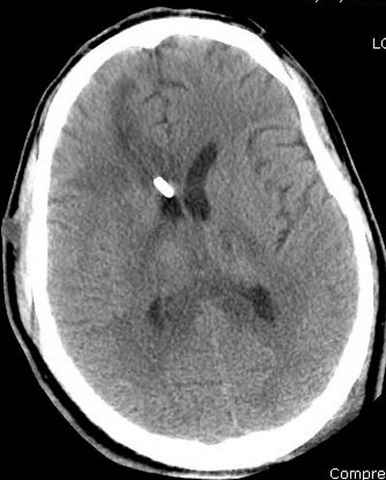

Наблюдается службой травмы и нейрохирургии (ICP) Increased Intracranial Pressure by ventricular cateter

больной без сознания, со слов нейрохирурга, наблюдается положительная динамика в нейрохирургическом статусе.

монииторинг

-Согласен, рана до прихода пластического хирурга была 38х13 см, можно было постараться закрыть сверху, а в нижнем отделе где был ожог, применить кожную пластику меньшим размером. К моему удивлению и разочарованию, когда вернулся из другой операционной (шли пареллельные операции), он уже успешно заканчивал свое дело. Кстати недавно разговаривал с нейрохирургом, он снял ICP (intracranial prеssure monitor), внутричерепное давление стабилизировалось, ортопеды и хирурги закончили с лечением, теперь длительное неврологическое восстановление.